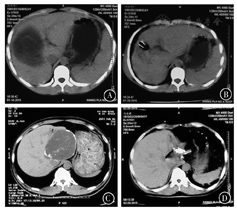

负压引流组35人,带管时间为(34.48 ± 12.46)d,明显少于对照组[33人,(54.27 ± 35.18)d,t=3.127,P< 0.05]。拨管时间负压引流组为7 d至3个月,对照组为7 d至5个月。与引流前比较,负压引流后患者残腔明显缩小(图1),且无残腔积液及感染,而对照组残腔积液及感染发生率分别为21%(7/33)、12%(4/33)。

A:CE3a型包虫病穿刺前CT影像图;B:CE3a型包虫病穿刺后负压引流CT影像图;C:CE4型包虫病穿刺前CT影像图;D:CE4型包虫病穿刺后负压引流CT影像图;CE:囊型包虫病